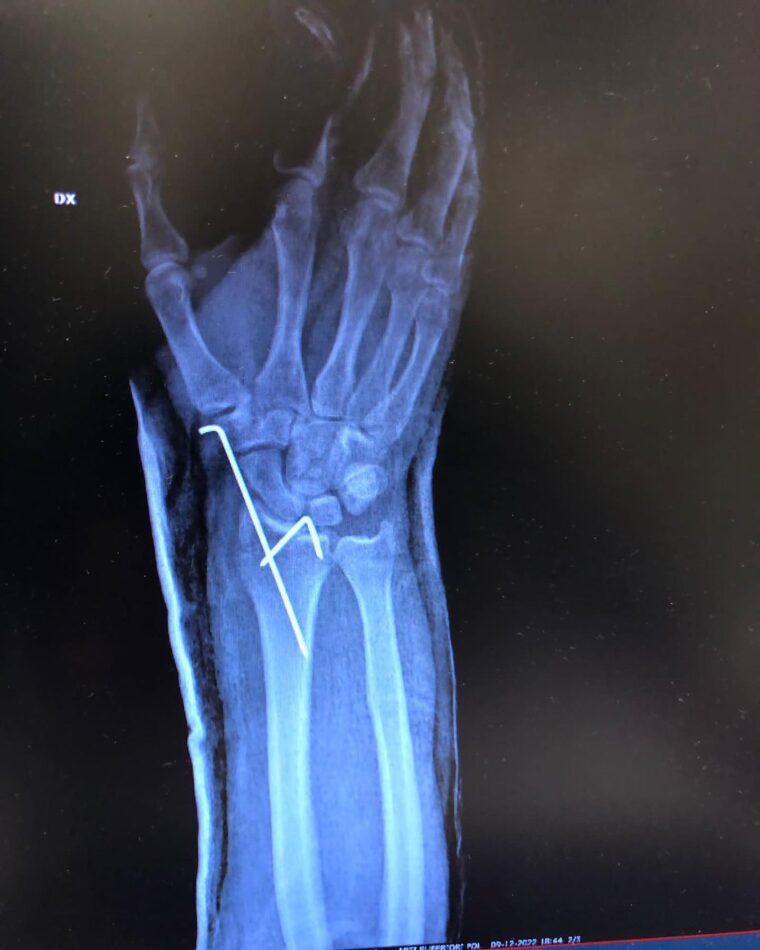

El propio Dovizioso compartió las imágenes en sus redes sociales, en las que mostraba la magnitud de la lesión y las radiografías de la muñeca completamente destrozada. El italiano tuvo que ser operado de urgencia para corregir la fractura, pero ya se recupera con vistas a retomar su actividad lo antes posible.

Aquí tienes todas las imágenes de una lesión que pone los pelos de punta: